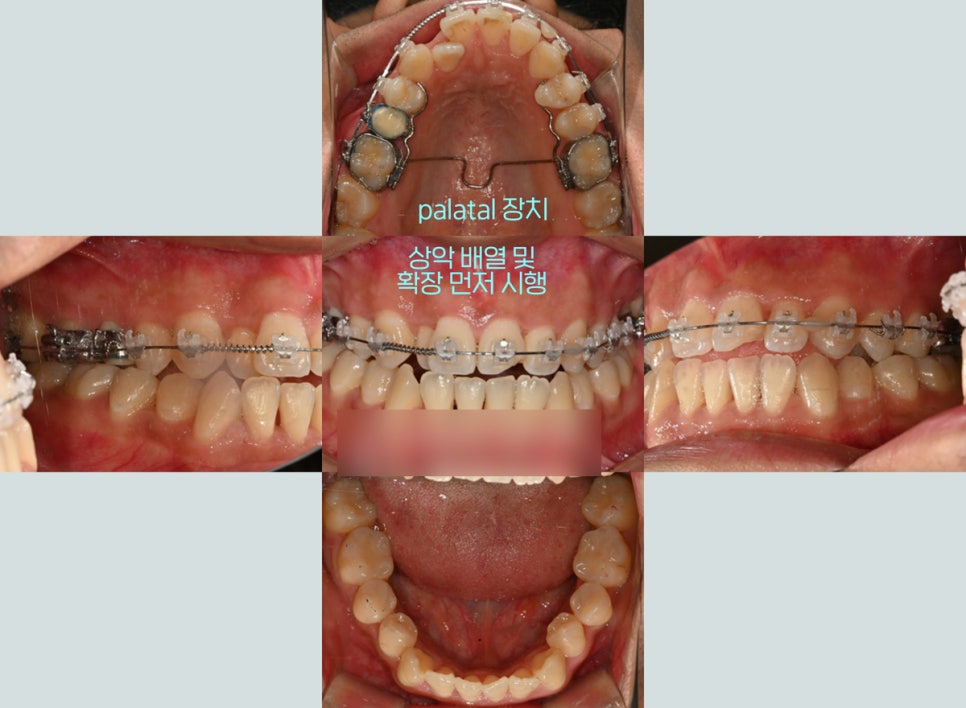

상악 확장 후, 전체 배열 시작

면목동 치과 에서는

심하게 썩은 곳부터 진료를 도왔는데요.

이후 상악 확장 장치를 부착하여

위쪽 공간을 확장한 뒤에,

전체 배열을 도와드리기로 했습니다.

우선 상악에만 장치를 부착했습니다.

이후 제위치를 찾을 수 있도록

어느 정도 공간이 확보된 후,

하악에도 장치를 연결하여 이동을 이끌었는데요.

점차 알맞은 교합을 찾아

개선이 되고 있는 것을 볼 수 있네요ㅎㅎ